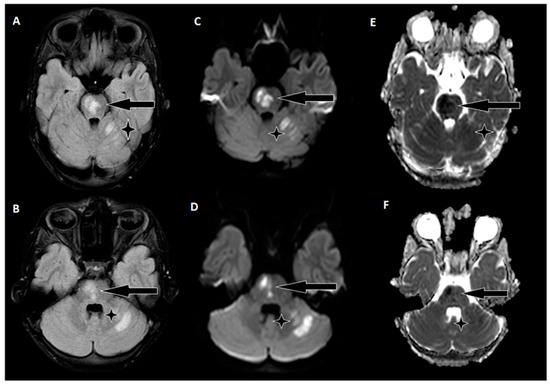

A 9-year-old male was admitted to a regional hospital due to a persistent complaint of diarrhea, exceeding ten episodes in two days, accompanied by a single episode of vomiting, tension headache, and mild vertigo. Initial diagnostic assessments did not reveal any notable abnormalities, leading to a diagnosis of gastroenteritis. Following rehydration therapy, the patient’s overall condition improved, and discharge plans were being considered. However, on the subsequent day after admission, at approximately 6 pm, the patient suddenly experienced weakness localized to the left side of his body. Recognizing the urgency of the situation, an emergency consultation with a neurologist was promptly arranged. Two hours following the onset of these new symptoms, a computed tomography (CT) scan of the brain was conducted (Figure 1), which did not show any acute changes in the brain. Nevertheless, the CT scan did reveal two hypodense regions in the left cerebellum, which raised suspicion of malignancy, along with a hyperdense appearance of the basilar artery (BA). Additionally, a hypodense region was noted in the left thalamic region, suggesting a potential prior lacunar stroke.

Figure 1. Emergency CT scan of the brain. (A) Hypodense region in the left thalamic region; (B) hyperdense basilar artery (HDBA) sign; (C) 2 hypodense regions in the left cerebellum.